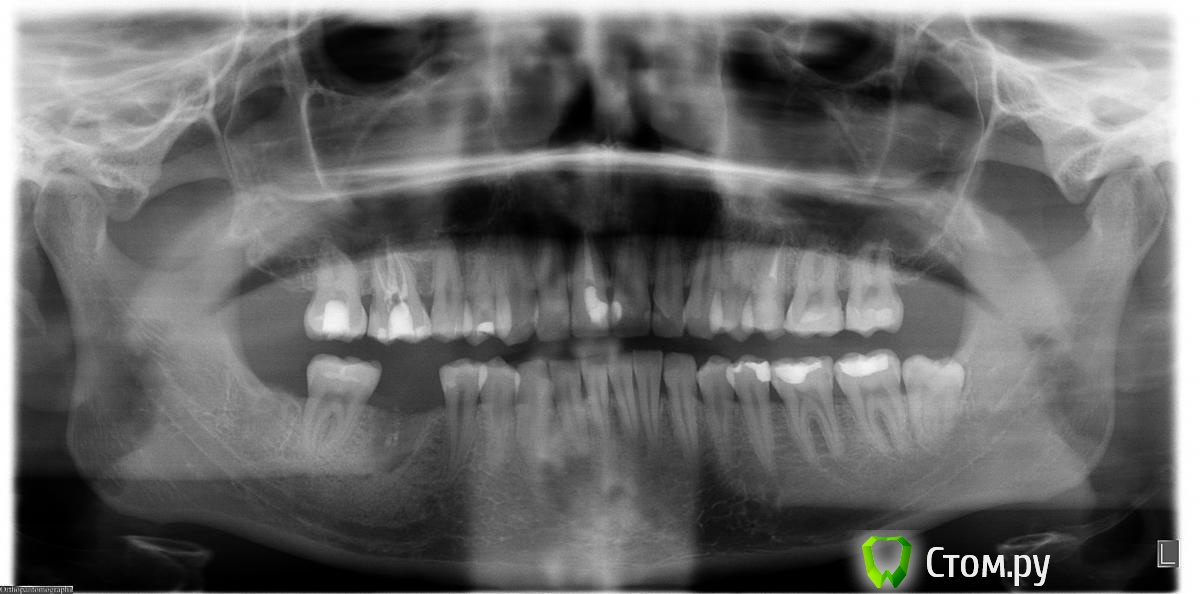

IvanK Опубликовано 12 марта, 2014 Поделиться Опубликовано 12 марта, 2014 Выложите панорамный снимок. Ссылка на комментарий

Юлия Арт Опубликовано 12 марта, 2014 Автор Поделиться Опубликовано 12 марта, 2014 снимок сделан в прошлом году, другого пока нет. нижняя 6-как и верхняя 5-ка удалены так как кисты под ними были.3 зуба с нервами за 2 дня депульпировали так как болело так что обезболивающее не брало... уже сомневаюсь что надо было это делать, хотя каналы кровили во всех зубах-пульпит был долгое время Ссылка на комментарий

Юлия Арт Опубликовано 13 марта, 2014 Автор Поделиться Опубликовано 13 марта, 2014 вот фото, панорамный сделали сегодня (вторая кист куда-то делась у верхней 5-ки, вырывать зуб не стали),троица с депульпцией болит и ноет сильно, есть на них не могу Ссылка на комментарий

anvladd Опубликовано 13 марта, 2014 Поделиться Опубликовано 13 марта, 2014 17 зуб похоже проблемный уж слишком пломба глубоко. Ссылка на комментарий

Л Ю С Я Опубликовано 13 марта, 2014 Поделиться Опубликовано 13 марта, 2014 1.4 перелечивать, разобраться с 1.7 и 1.5, возможно и 1.6 проблемный Ссылка на комментарий

anvladd Опубликовано 13 марта, 2014 Поделиться Опубликовано 13 марта, 2014 Нерв удалили в 16 а вот 17 судя по снимку под подозрением. И как писала доктор выше 14 перелечивать каналы. Ссылка на комментарий

Юлия Арт Опубликовано 13 марта, 2014 Автор Поделиться Опубликовано 13 марта, 2014 (изменено) уважаемые, уже третий день после начала депульпации 7, 6(завершено) и 4-го верхних болит вся цека и все зубы 7-6-5-4...есть на них не могу, такое ощущение что их распирает изнутри, если стучать по ним-небольно, но есть неокторые места куда если пища попадает или пальцем надавить - стреляет больно! через 2 недели только приём у врача на завершение депульпации... а я ждать не смогу, отнимается левая верхняя сторона. судя по фото, что там может быть? или нервы в зубах или , может, они поломаны или десна воспалены? воможности КТ сделать пока нет Изменено 13 марта, 2014 пользователем Юлия Арт Ссылка на комментарий

Mane Опубликовано 13 марта, 2014 Поделиться Опубликовано 13 марта, 2014 По снимкам в проведенных манипуляциях криминала нет. Запасайтесь обезболивающими и ждите. Должно пройти. Если доктор сделал все правильно - весь протокол - то все пройдет. Ссылка на комментарий

anvladd Опубликовано 13 марта, 2014 Поделиться Опубликовано 13 марта, 2014 уважаемые, уже третий день после начала депульпации 7, 6(завершено) и 4-го верхних болит вся цека и все зубы 7-6-5-4...есть на них не могу, такое ощущение что их распирает изнутри, если стучать по ним-небольно, но есть неокторые места куда если пища попадает или пальцем надавить - стреляет больно! через 2 недели только приём у врача на завершение депульпации... а я ждать не смогу, отнимается левая верхняя сторона. судя по фото, что там может быть? или нервы в зубах или , может, они поломаны или десна воспалены? воможности КТ сделать пока неттак потому и болит что,как я понимаю,не завершена депульпация 7 и 4 зубов. Вы вложили снимок до или после депульпации, напишите. 1 Ссылка на комментарий

Юлия Арт Опубликовано 14 марта, 2014 Автор Поделиться Опубликовано 14 марта, 2014 так потому и болит что,как я понимаю,не завершена депульпация 7 и 4 зубов. Вы вложили снимок до или после депульпации, напишите.всё верно понимаете, у 6-го каналы вроде почистили, хотя я тут начиталась что их там 4-ре, врач нашёл только 3. 6-й тоже болит сильно, они вообще все с 7-го по 4-й дружно ноют и стреляют. скорее всего там не просто пульпит был, но и периодонтит судя по моим симптомам Ссылка на комментарий

anvladd Опубликовано 14 марта, 2014 Поделиться Опубликовано 14 марта, 2014 тогда долечивать 7,4 и перелечивать 6,искать 4й канал. удачи. Ссылка на комментарий